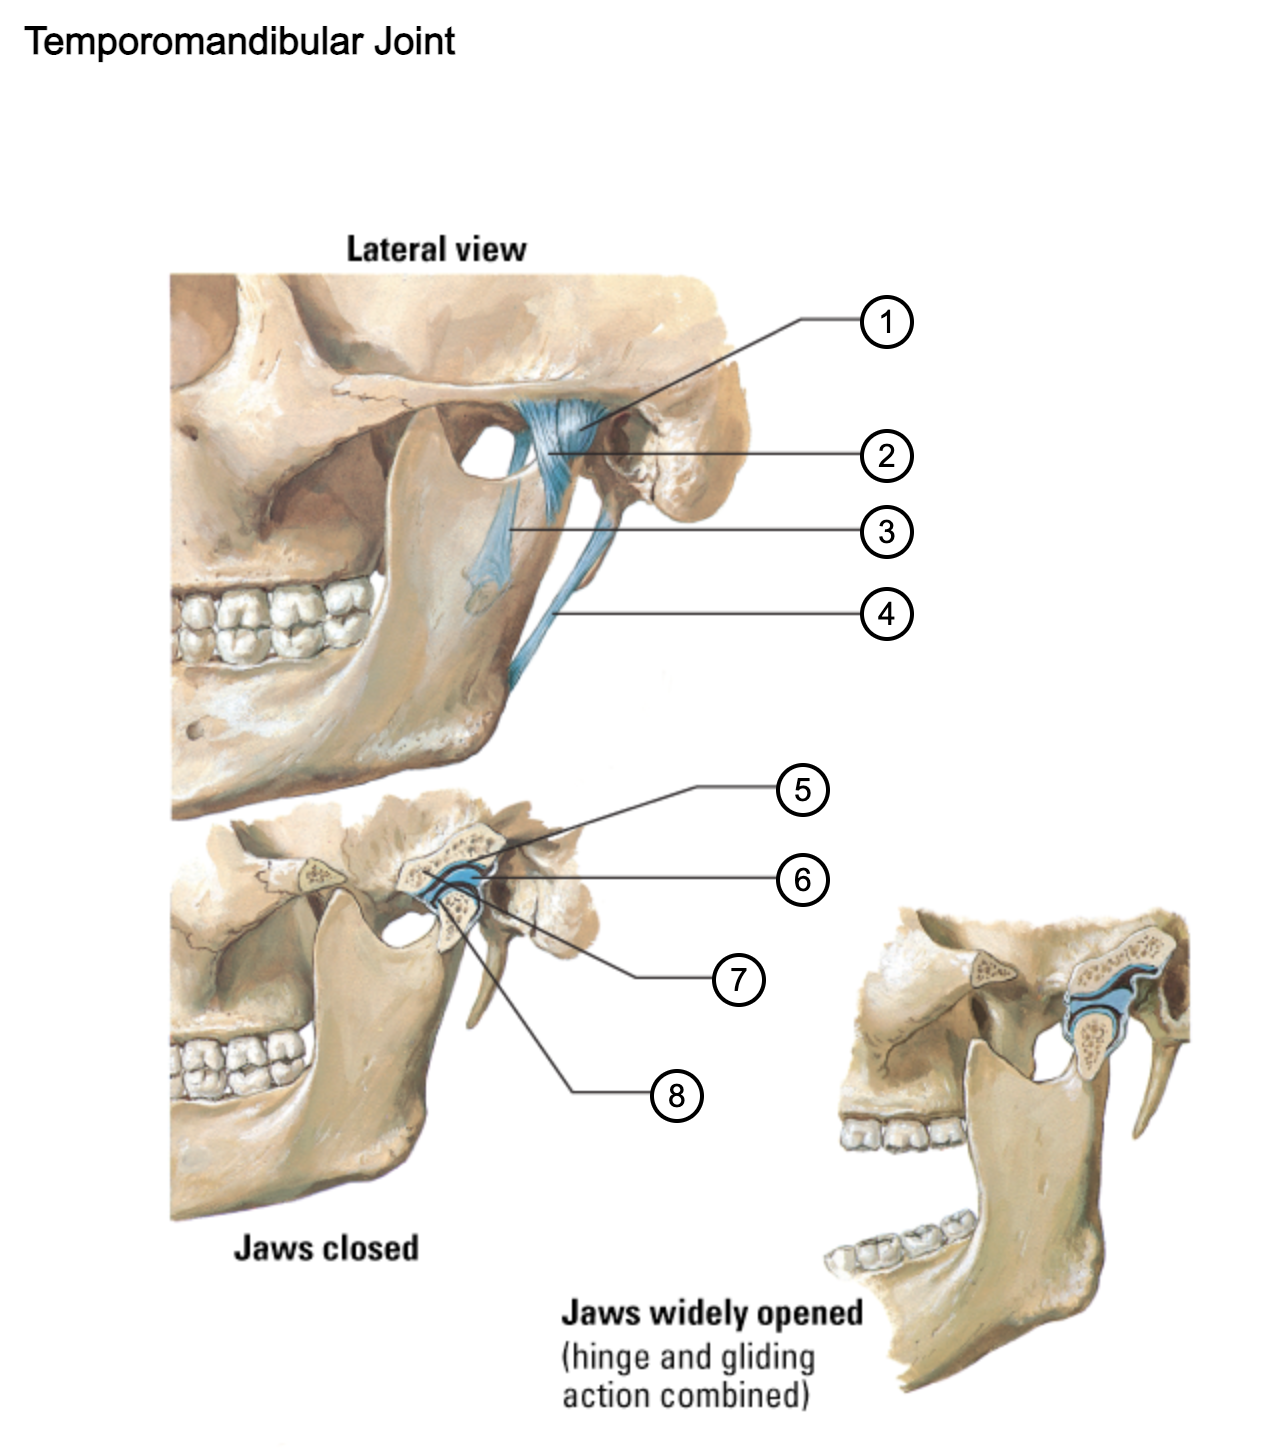

1

capsule of temporomandibular joint

2

lateral temporomandibular ligament

3

sphenomandibular ligament

4

stylomandibular ligament

5

mandibular fossa

6

articular disc

7

articular tubercle

8

capsule of temporomandibular joint